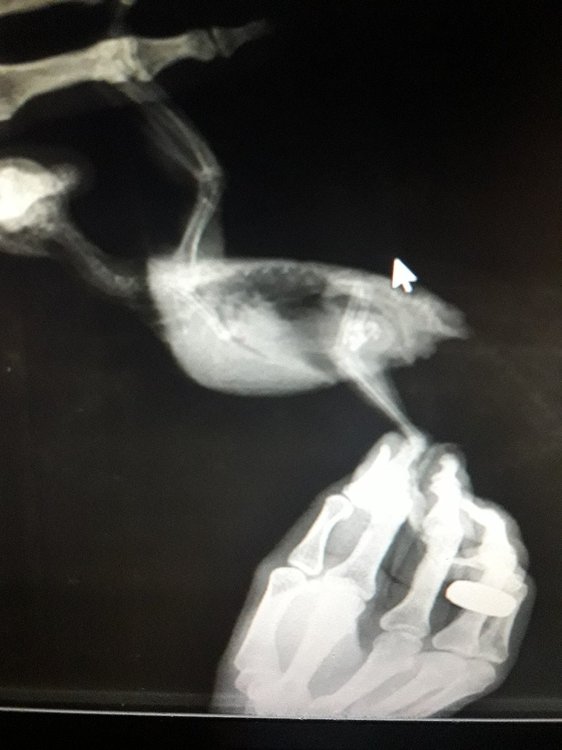

Малыш 87 Опубликовано 12 декабря, 2019 Автор #23 Опубликовано 12 декабря, 2019 Делали ренген Сказали вроде как немного увеличена

Малыш 87 Опубликовано 13 декабря, 2019 Автор #28 Опубликовано 13 декабря, 2019 Мне отдали только диск с ренгеном

Кузяныч Опубликовано 13 декабря, 2019 #31 Опубликовано 13 декабря, 2019 @Малыш 87, а результаты анализа помёта на листе бумаги вам выдавали на руки? Все эти расспросы я затеял потому что при увеличении печени (гепатомегалии) больше подходит гепатовет. Гептрал, как по мне, назначают при явных тяжёлых поражениях, одним из симптомов которых является помёт жёлтого / оранжевого цвета. И ещё я хотел бы увидеть результат анализа помёта чтобы сопоставить их с внешним видом помёта на предоставленном вами снимке.